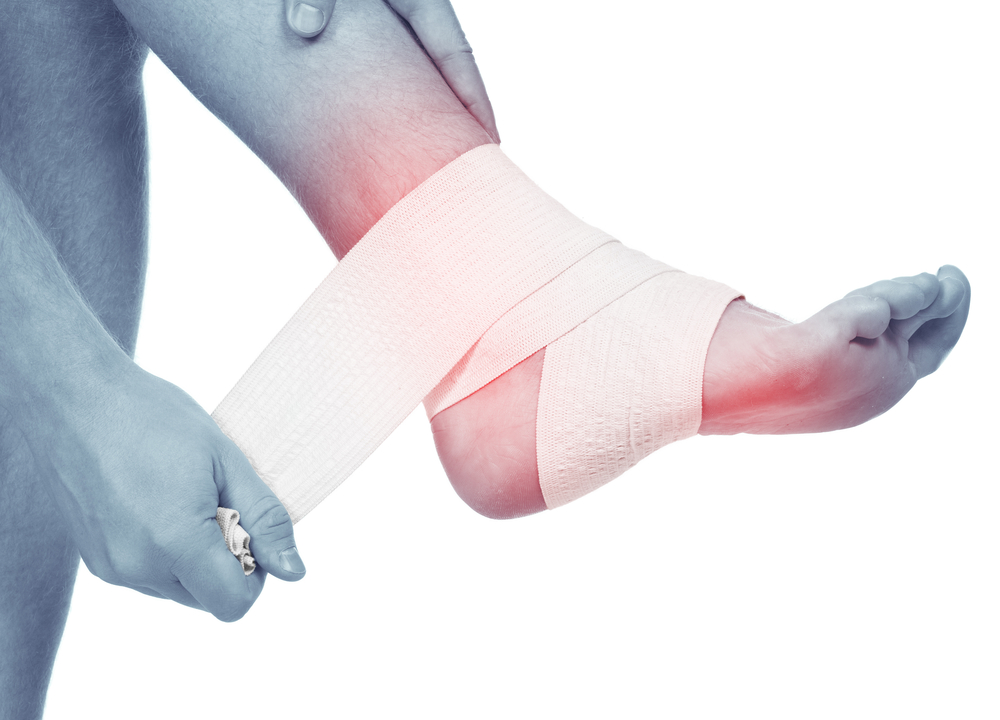

Dislocation:A dislocation is the movement of a bone at a joint from its normal position. When the bone is moved out of place, the joint no longer functions. Usually, dislocations happen at the shoulder, elbow, wrist, jaw and hip. Sprain / Strain:A sprain is the tearing of the ligaments at a joint. Sprains mostly occur at the ankle, knee, wrist and fingers. A strain is the stretching and tearing of a muscle. They usually occur in the neck, back, thigh, or the back of the lower leg. Use RICE method when dealing with a sprain or strain:

Rest: Do not move or straighten the injury. Immobilize: Try to stabilize the person in the position he/she was found. Splint or sling the injured part only and use caution if moving the person. Cold: Indirectly cool the part using ice for up to 20 minutes. Elevate: Only elevate the part if it does not cause more pain. First Aid Actions / Treatment:

A sprain is the tearing of the ligaments at a joint. Sprains mostly occur at the ankle, knee, wrist and fingers. A strain is the stretching and tearing of a muscle. They usually occur in the neck, back, thigh, or the back of the lower leg.

Use RICE method when dealing with a sprain or strain:

Rest:

Do not move or straighten the injury.

Immobilize:

Try to stabilize the person in the position he/she was found. Splint or sling the injured part only and use caution if moving the person.

Cold:

Indirectly cool the part using ice for up to 20 minutes.

Elevate:

Only elevate the part if it does not cause more pain.